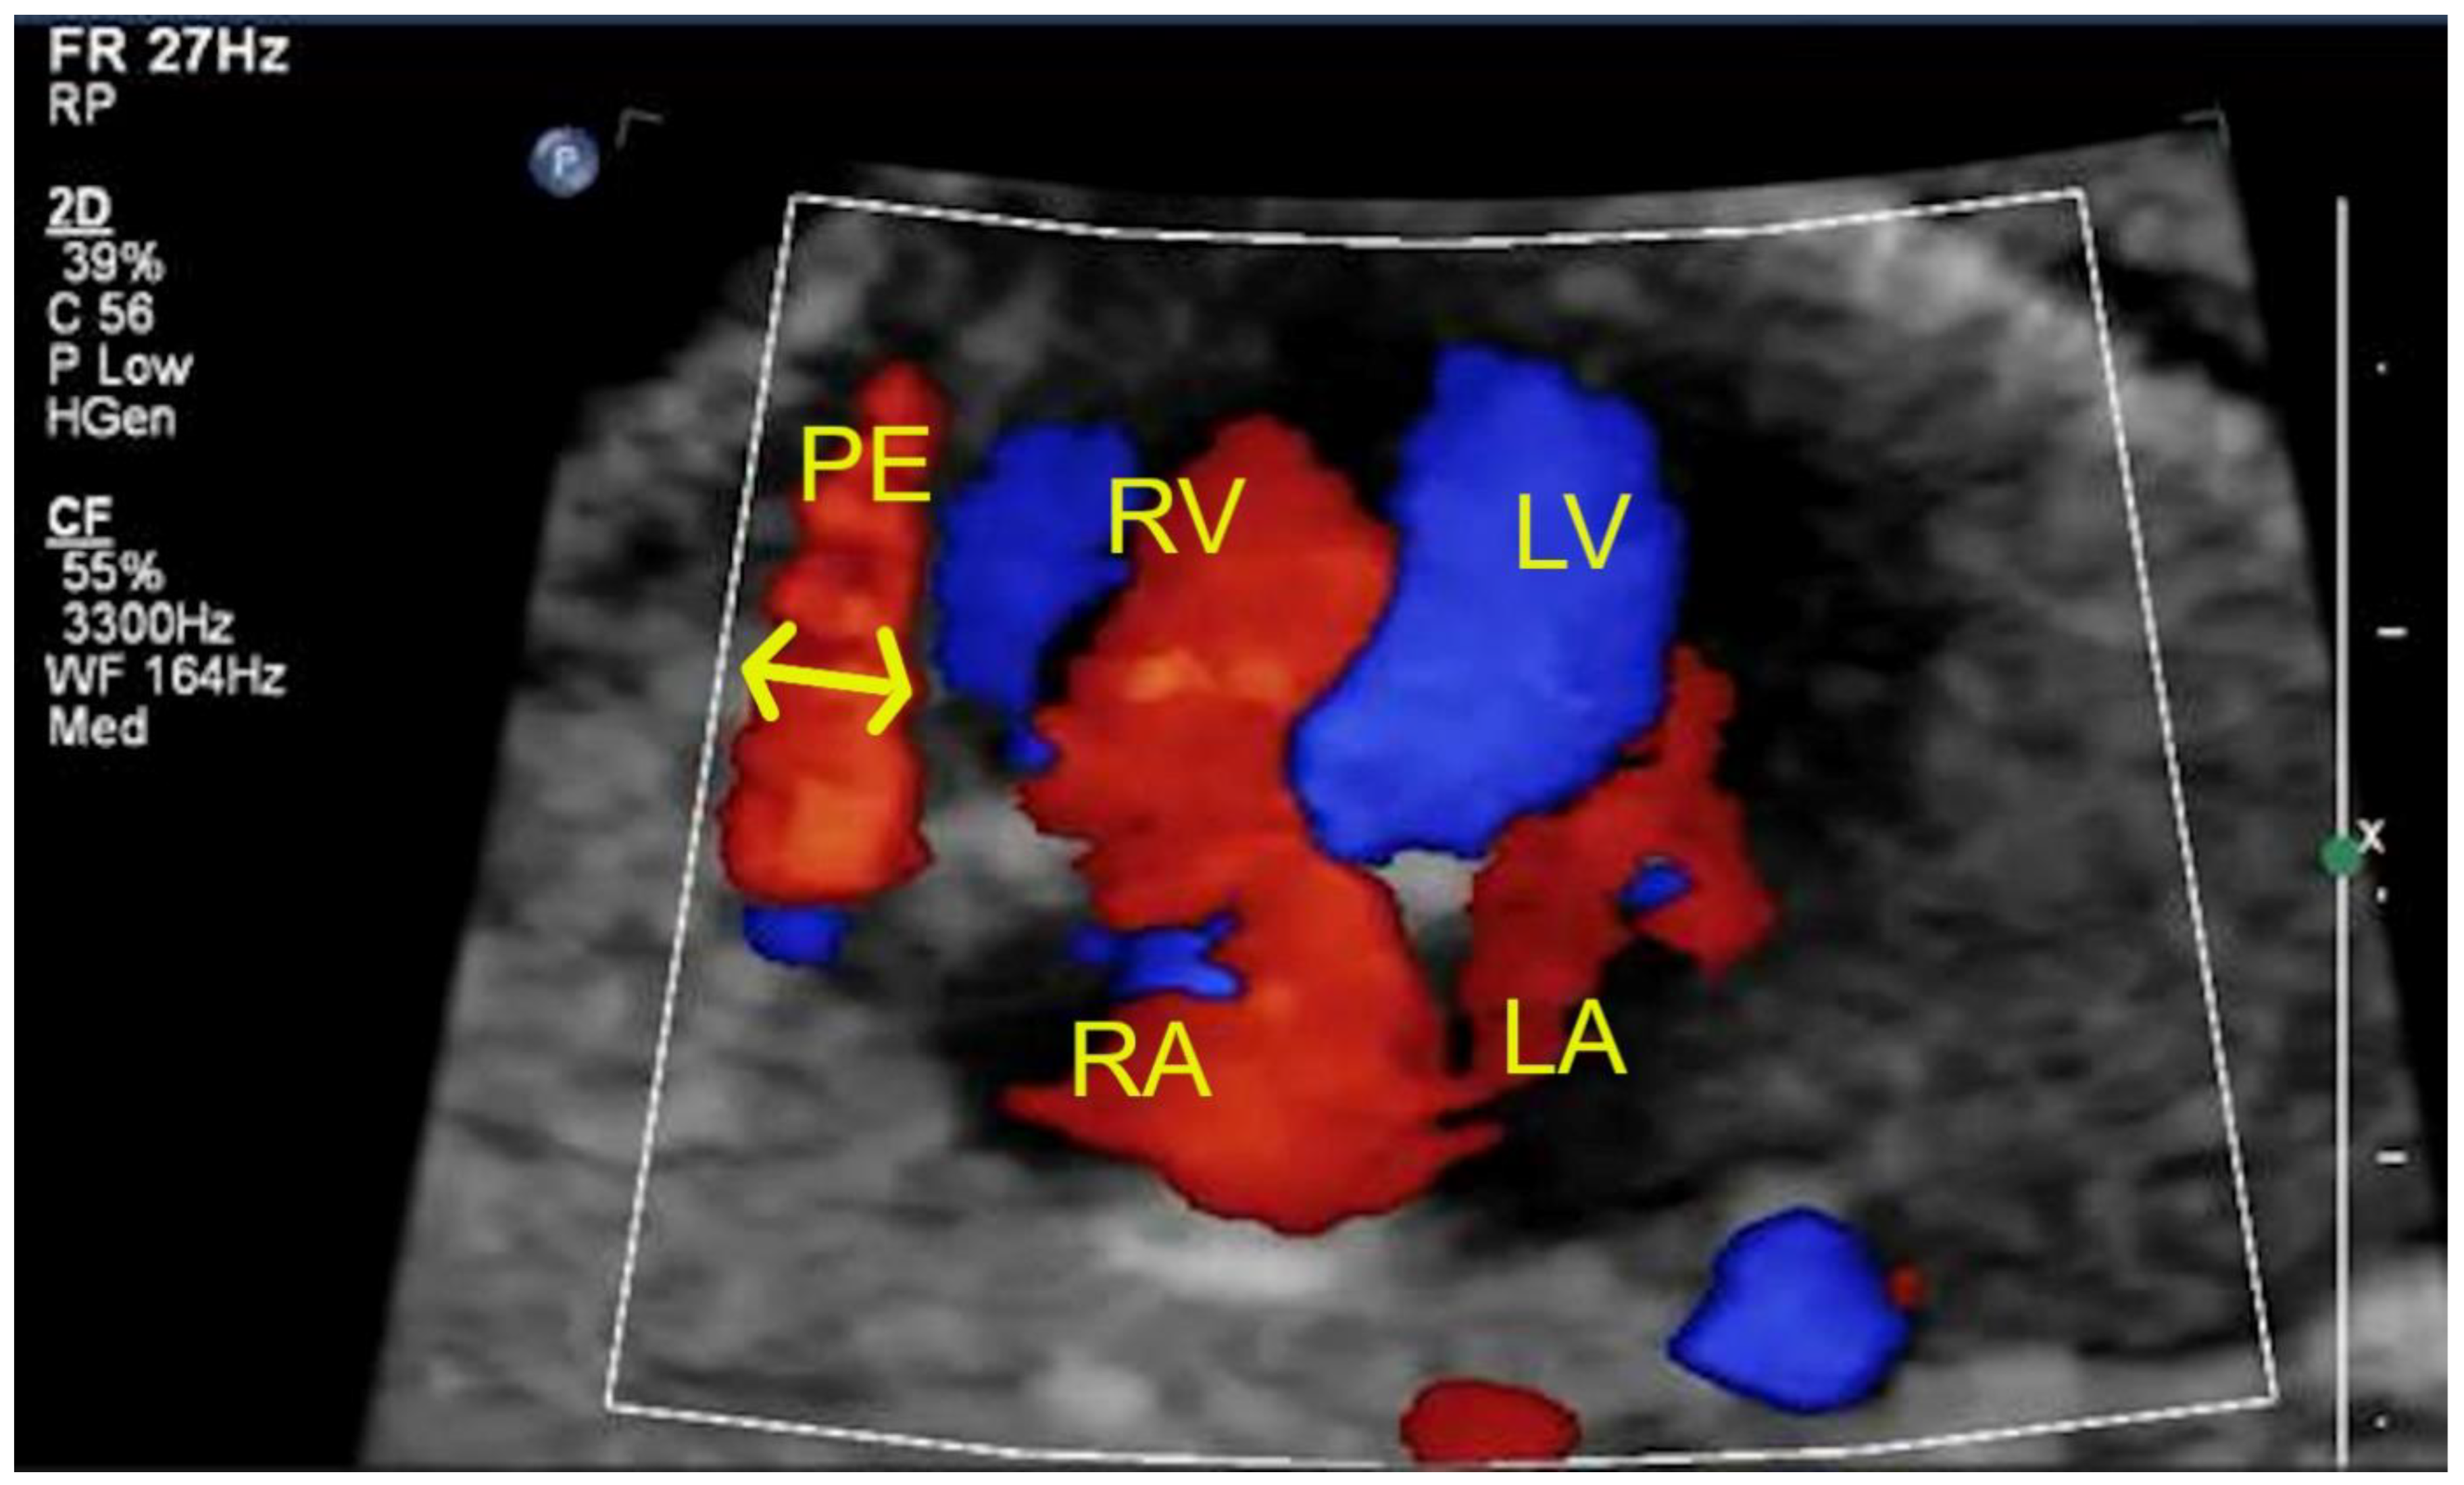

| Tricuspid insufficiency (in color and in spectral Doppler) | 2 | 8 | 2 |

| Pericardial effusion (>2 mm) | 1 | 4 | - |